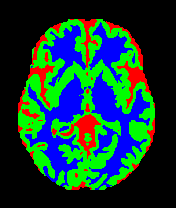

8 Class Activation Map (CAM) Analysis

Since class activation maps (CAM) visualization can provide visual explanations for understanding model performance, we incorporate CAM visualization as a tool to analyze the discriminative regions used by our models. We compare the performance of baseline augmentation strategies against their ”Ours+” enhanced counterparts. Fig. 11 and Fig. 12 illustrate the CAMs generated from models trained on the OASIS-1 and MRBrainS13 datasets. It is visually evident that the baseline models’ (e.g., rows 1, 3, 5) regions of interest are often highly diffuse and noisy. They cover irrelevant textures or artifacts and seem distracted from the core anatomical structures, indicating a potential overfitting problem and poor generalization. In contrast, after utilizing our framework, the ”Ours+” models (rows 2, 4, 6) are more inclined to locate and highlight the most relevant parts of the target anatomy (e.g., Gray Matter or White Matter). These methods’ regions of interest are significantly more focused, structurally coherent, and precisely localized, while ignoring much of the spurious background information. This indicates a better generalization ability. To summarize, these visualizations underscore how our framework surpasses the efficacy of the original augmentation methodologies, forcing the model to learn true, generalizable anatomical representations, which in turn explains the more robust and accurate segmentation performance.